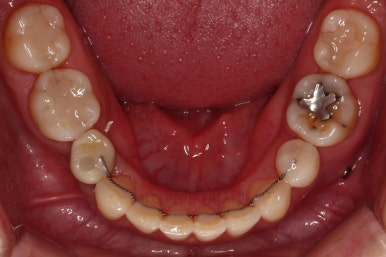

임플란트 보철까지 잘 세팅이 된 후 마무리 하게 되었습니다.

임플란트까지 잘 들어간 후 마무리 했고요.

결손공간 없이 상하좌우 모두 같은 갯수의 치아로 치료가 잘 종료되었습니다.

부산인비절라인 전후 비교해 볼게요.

얼굴에 대한 중앙선도 잘 마무리 되었습니다.

어쨌든 모든 부분에서 인비절라인으로 잘 마무리가 된 환자분이었습니다.

이상 결손치아가 5개 있었고, 비대칭, 유치잔존 환자분을 부산인비절라인으로 교정치료 후 임플란트 2개로 마무리를 한 치료사례였습니다.